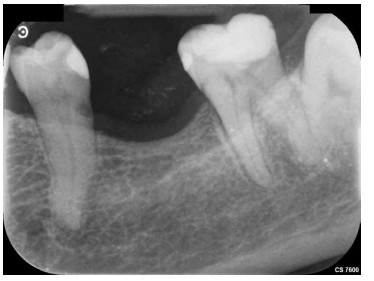

Se continuó con la remoción no selectiva de la caries y de la restauración previa con fresas redondas de turbina y contraángulo (Figura 3). Posteriormente, se expuso la pulpa en la zona más cercana a la lesión en una extensión de unos 2-3 mm con una fresa estéril redonda de diamante montada en turbina con abundante refrigeración. Se observó la pulpa y la sangre era roja brillante (Figura 4). Se controló el sangrado con una bolita de algodón embebida en hipoclorito de sodio 3% que se aplicó durante 2 minutos (Figura 5).